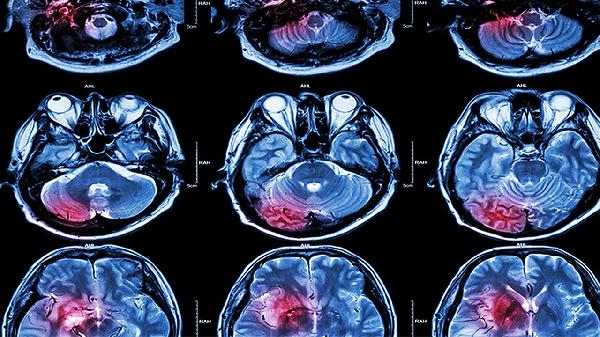

宝宝脑发育迟缓有哪些表现

宝宝脑发育不全的表现通常包括运动发展缓慢、肌肉张力异常、语言能力不足、认知功能受限以及癫痫发作等。这种状况可能由遗传因素、产前或产时缺氧、颅内感染、代谢问题或脑部外伤等多种原因引起,通常会表现出上述症状中的一个或多个。建议家长尽早带孩子接受专业检查,早期干预对改善预后有积极影响。